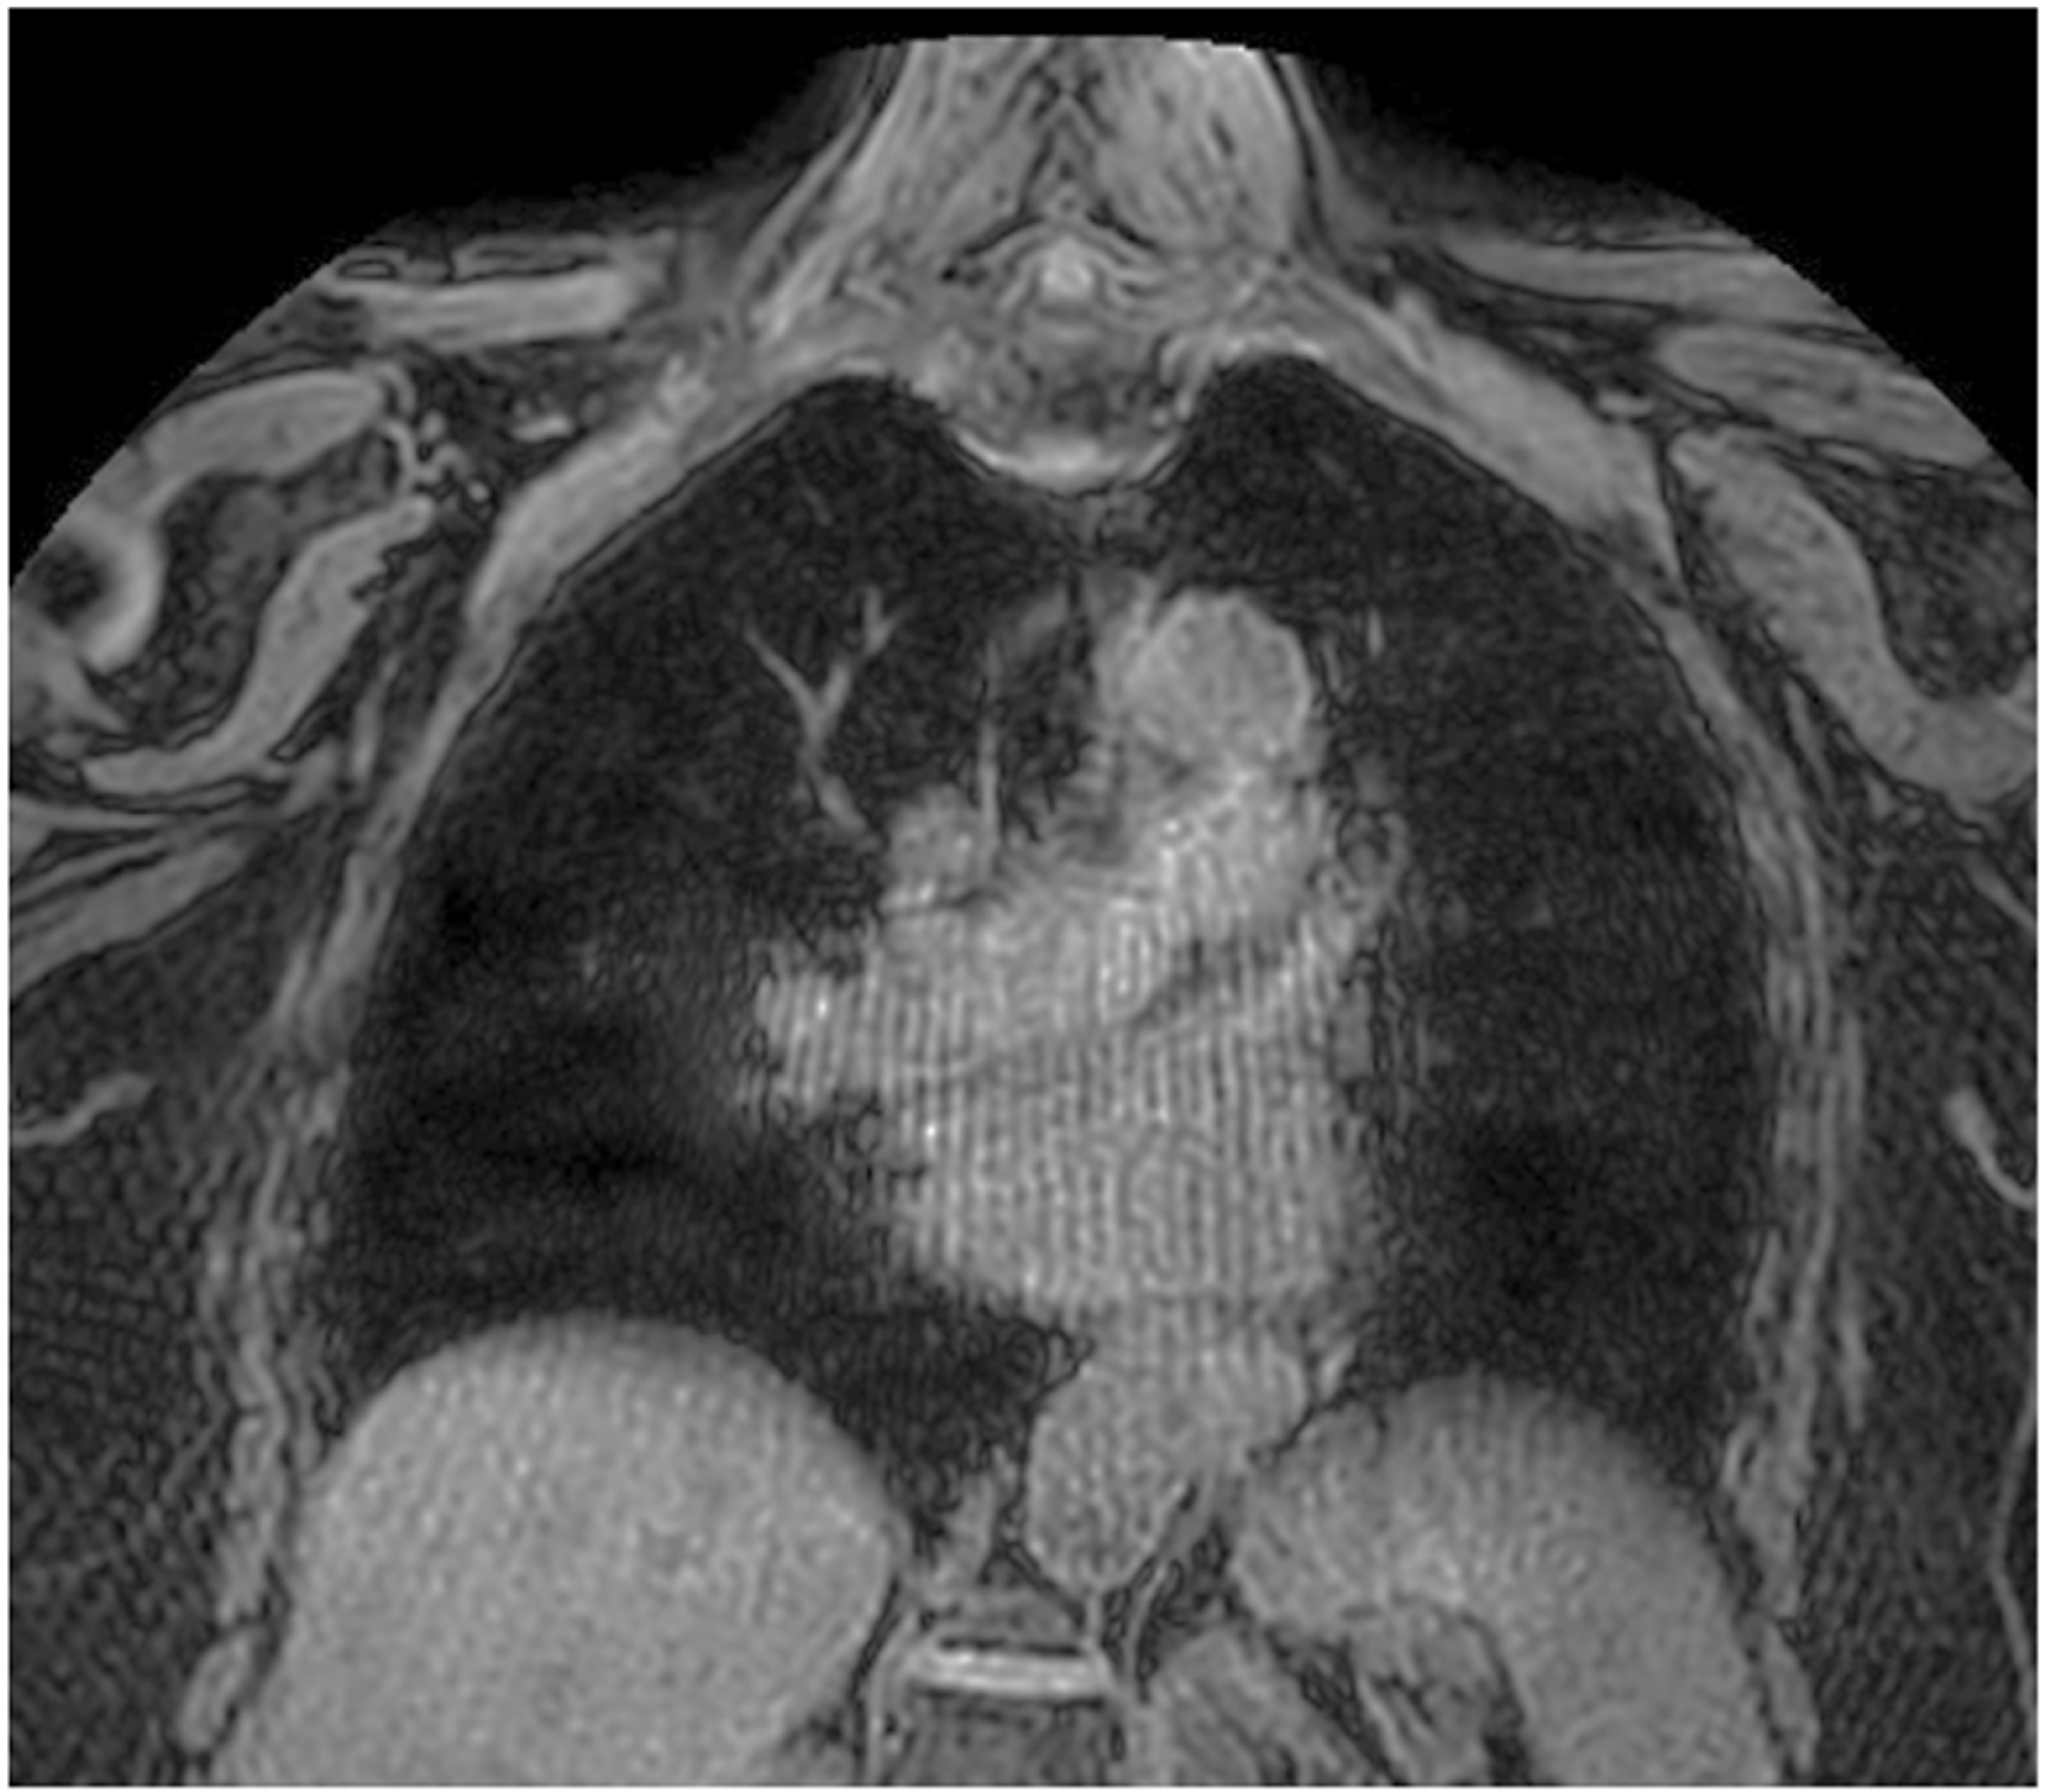

- Tischendorf, P.; Kunnemann, M.D.; Krahling, T.; Lange, J.H.; Heindel, W.; Beck, L. Thoracic MRI in Pediatric Oncology: Feasibility and Image Quality of Post-Contrast Free-Breathing Radial 3D T1 Weighted Imaging. Biomedicines 2025, 13, 2302. [Google Scholar] [CrossRef]